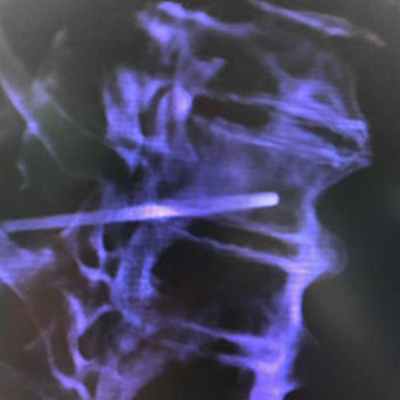

• При патологических переломах применяют внутреннюю фиксацию в комбинации с металлическими имплантатами и метилметакрилатным костным цементом для закрытия дефекта кости.

Хирургическое вмешательство для стабилизации кости часто проводится для лечения переломов и иногда даже для профилактики переломов. Хирургическое вмешательство при патологических переломах может включать введение стержня в кость, использование пластин и винтов для стабилизации кости или удаление пораженной кости с реконструкцией конечности и сустава.